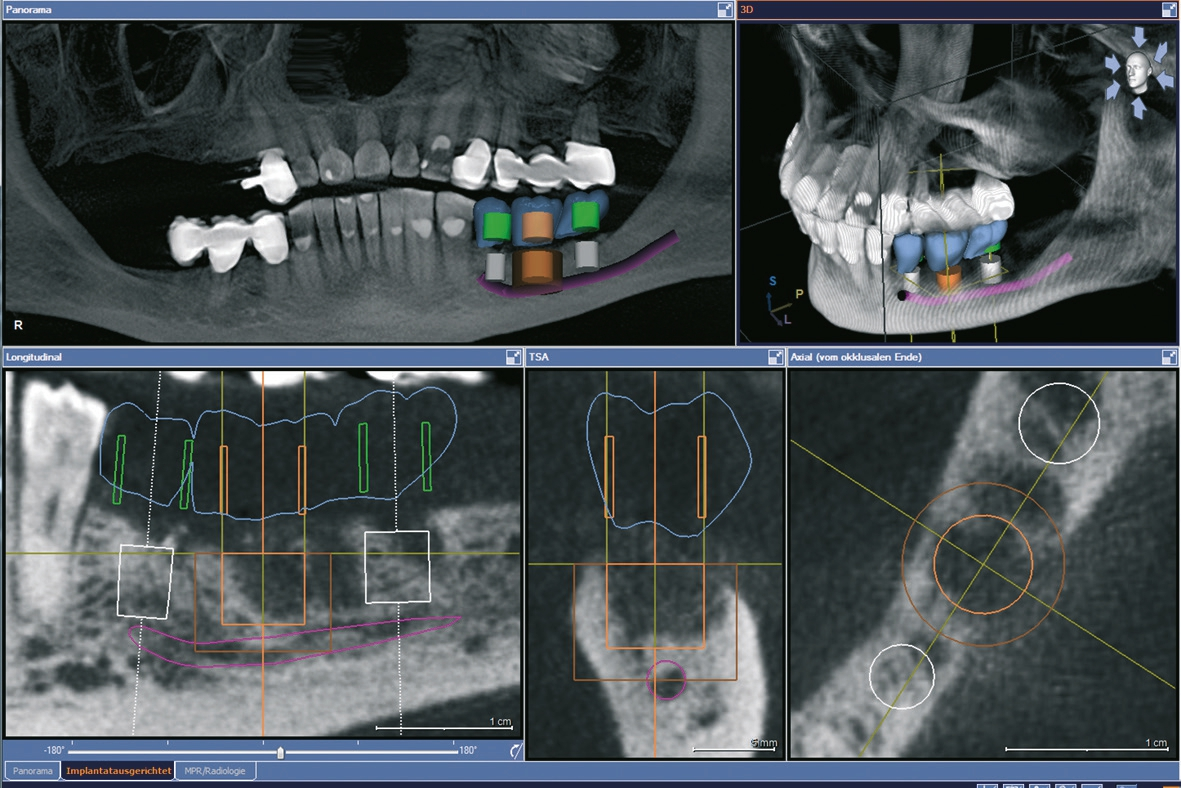

Eine der häufigsten Indikationen für Implantate überhaupt stellt die Einzelzahnlücke nach Verlust eines ersten Molaren dar. Bei den meisten Fällen liegt ein stabiles vertikales Knochenangebot an den Nachbarzähne vor, sodass in der Regel nach Ausheilung des apikalen Granulationsgewebes von einer guten Knochenregeneration auszugehen ist, so dass keine Notwendigkeit der Insertion von kurzen oder ultrakurzen Implantaten gegeben ist. Im Oberkiefer kann bei einer weiten Divergenz der Wurzeln des extrahierten Zahnes es zu einer ausgeprägten Pneumatisation der Kieferhöhle kommen. Daher werden gerade beim jugendlichen Patienten dort dann kurze Implantate eingesetzt, um auf eine Sinusbodenelevation mit einem lateralen Zugang verzichten zu können [3]. Die Implantate können mit oder ohne eine Navigationsschablone gesetzt werden [4]. Da die Lücke begrenzende Nachbarzähne eine gute Orientierung in der mesio-distalen Dimension ermöglichen, kann oftmals auch auf eine Orientierungsschablone verzichtet werden. In der oro-vestibulären Richtung muss der Anwendung des größeren Durchmessers Rechnung getragen werden. Dies kann mit einfachen Positionierungshilfen erfolgen, damit die Implantatachse möglichst zentral in der Kaufläche zu liegen kommt (Abb. 1-8). Die Einzelzahnlücke kann mit einer integrierten verschraubbaren Abutment-Hybrid-Krone oder mit einem Abutment und einer zementierten Krone versorgt werden [5].